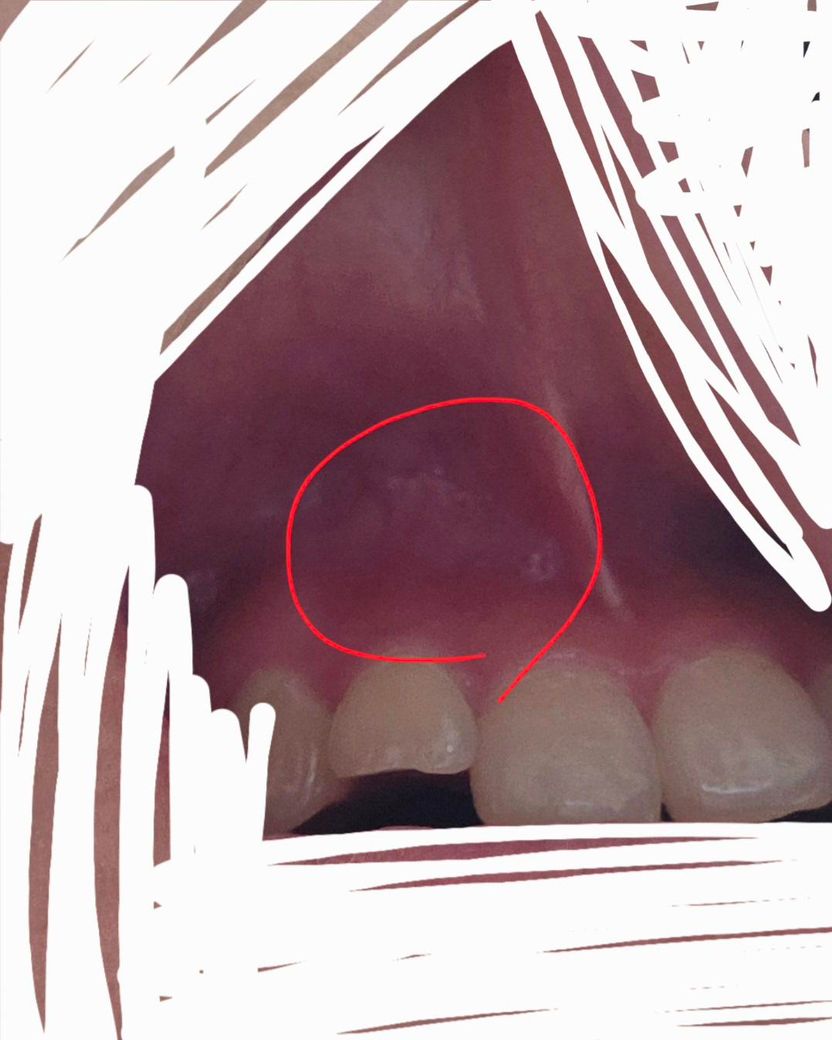

입천장에 염증 생기거나 헐었나요?ㅜㅜ

힘이 가해지면 아픈데 잇몸염증으로 어제 약 타왔고 위ㅜ앞니쪽 위주로 잇몸치료도 했어요

그거랑 연관된건지 아니면 별개로 헐거나 천장에도 염증이 생긴 건지 모르겠네요ㅜㅜ

사진상 제일 앞 볼록한 선? 같은 것과 두번째 사이 저 안쪽이 아파요

아 여기도 염증있는 건가요?

약간 하얀게 점같이 있는 것 같기도 한데 ㅜㅜ

염증은 아닌 것 같습니다. 치료를 받고 계신 것이라면 일단 치료받고 기다려보셔야 합니다.

상처가 좀 난 것으로 보이긴 합니다만 아직 치료도 남으셨고 치료 받으신지 얼마 안되셨으니 치료 종결될때까지 마음의 여유를 가지시길 바라겠습니다.

저부위는 염증보다는 음식등이나 뜨거운거에 자극을 받아서 그런거 같습니다. 시간이 지나면 괜찮아 지니 너무 걱정하지마세요.

사진상 봤을때 입천장 부위가 약간 염증이 있어보이긴 하네요. 잇몸치료를 한번 받으셨고, 후속 조치를 또 받으시니 이어서 치료 잘 받으시고 경과를 지켜보면 되겠습니다. 미노클린 이용하여 항생제 처치도 추가적으로 하면 좋을 것 같습니다.